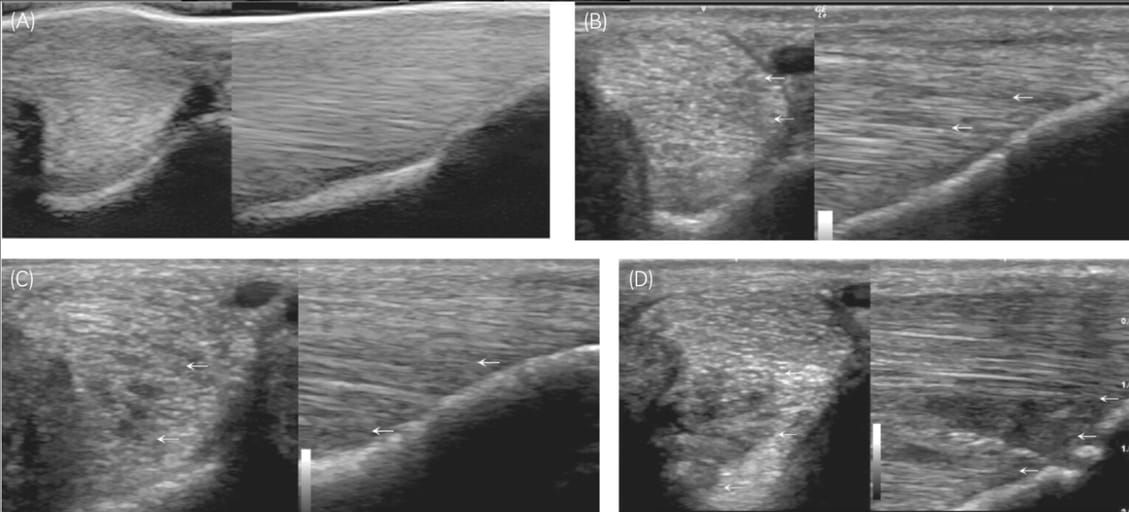

Examples of the grading system for the ultrasonographical appearance of the fibrillar pattern in the insertional region of the equine suspensory ligament branch. (A) Grade 0 fibrillar pattern: Homogenous echogenicity and uninterrupted fibrillar pattern. (B) Grade 1 fibrillar pattern: Regions of mild hypoechogenicity and/or small areas of subtly irregular fibrillar pattern, seen here as an indistinct hypoechoic region in the abaxial portion of the branch. (C) Grade 2 fibrillar pattern: Regions of moderate hypoechogenicity and/or focal areas of mild-moderately disrupted fibrillar pattern. (D) Grade 3 fibrillar pattern: Regions of severe hypoechogenicity/anechoic areas and/or extensive fibrillar disruption, large core lesion(s).